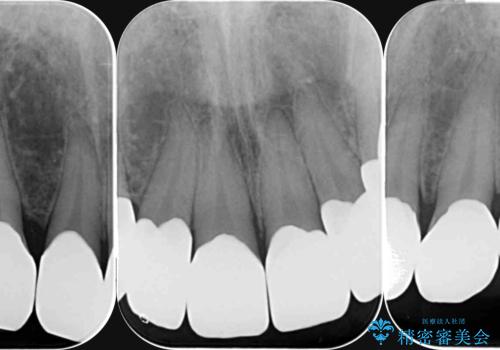

- 歯ぎしり・嘔吐症により歯がすり減ってしまい、色調・見た目を改善したいと来院されました。

神経を温存したまま仮歯に置き換え、噛み合わせの安定を確認したのちに すり減りに強いジルコニアクラウンで最終的な仕上げを行います。

歯の形態・色調を大きく変更する場合ジルコニアクラウンによる治療が耐摩耗性・審美性の観点から推奨されます。